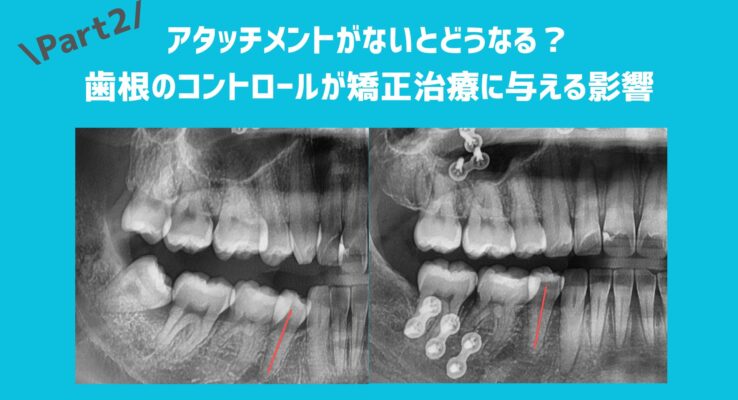

前回のブログでは、

アタッチメントの必要性や歯根の位置の重要性についてお話ししました。